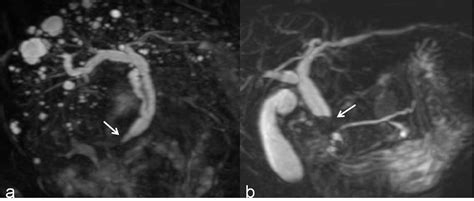

At its core, the MRCP utilizes the same technology as a standard MRI machine but is specifically calibrated to highlight fluids—like bile and pancreatic juices—in your body. Because these fluids are bright on the images produced, the ducts carrying them become highly visible. This is why medical professionals consider it the gold standard for visualizing the biliary tree and the pancreatic ductal system. It is essentially a high-tech map that helps doctors identify blockages, strictures, or anatomical variations that could be causing you discomfort.